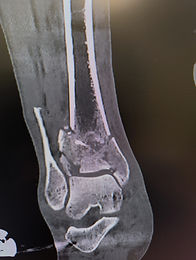

Ασθενής 32 ετών, υπέστη κάταγμα της δεξιάς ποδοκνημικής άρθρωσης στο θαλάσσιο σκι. Οι ακτινογραφίες ανέδειξαν συντριπτικό ενδοαρθρικό κάταγμα του κάτω πέρατος της κνήμης και κάταγμα της περόνης. Τοποθετήθηκε άμεσα εξωτερική οστεοσύνθεση προκειμένου να σταθεροποιηθεί το κάταγμα , να πραγματοποιηθεί αξονική τομογραφία και να προγραμματιστεί το χειρουργείο.

Ακολούθησε αφαίρεση της εξωτερικής οστεοσύνθεσης και ανοικτή ανάταξη του κατάγματος με τη διενέργεια δυο τομών του δέρματος. Τα οστικά τεμάχια ανατάχθηκαν, ανακατασκευάστηκε η αρθρική επιφάνεια και τοποθετήθηκε οστικό μόσχευμα προκειμένου να υποστηριχθεί ο υποκείμενος χόνδρος. Τα μικρά θραύσματα αφαιρέθηκαν από την άρθρωση και ακολούθησε σταθεροποίηση του κατάγματος με τη χρήση διαφορετικών πλακών.

Επετεύχθη εξαιρετική αποκατάσταση της αρθρικής επιφάνειας και ανατομική ανάταξη του κατάγματος.